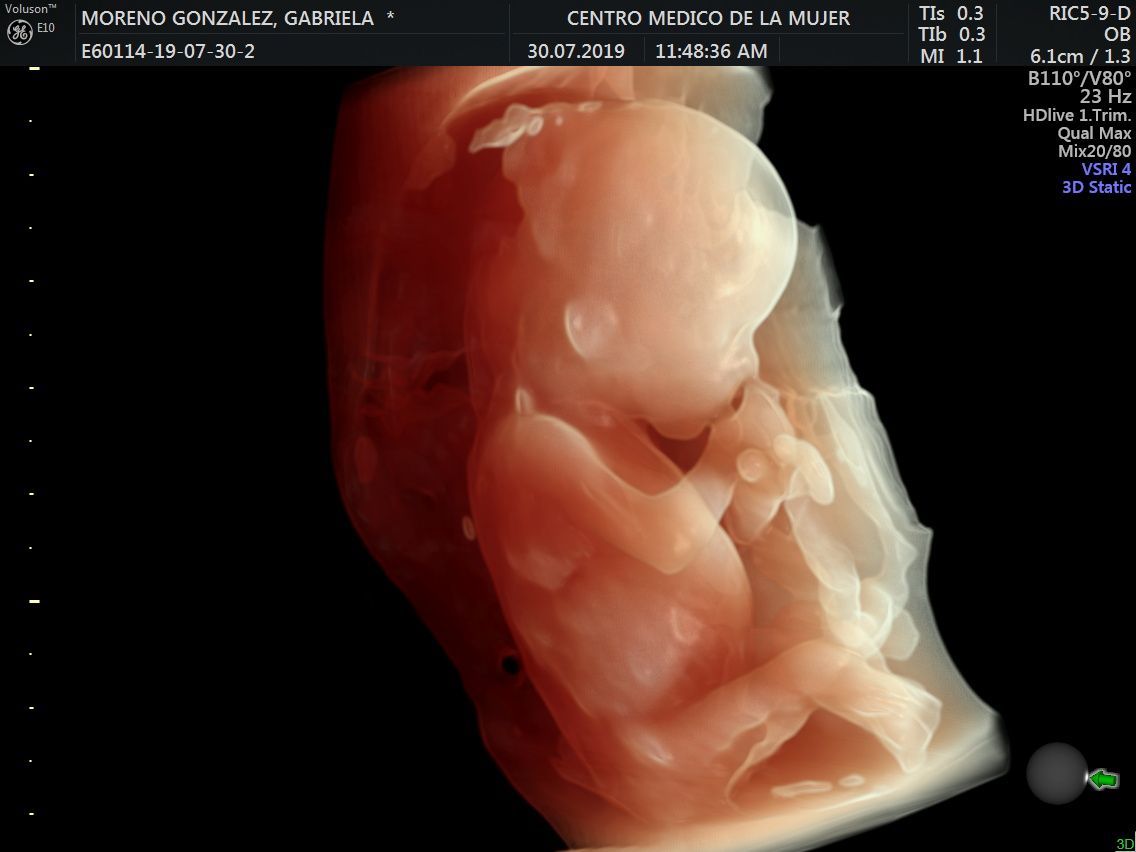

Fotos y videos

ECO Anatómico

Consiste en la evaluación especifica de cada organo y sistema del bebé con medidas detalladas de cada parte para evaluar su crecimiento proporcional.